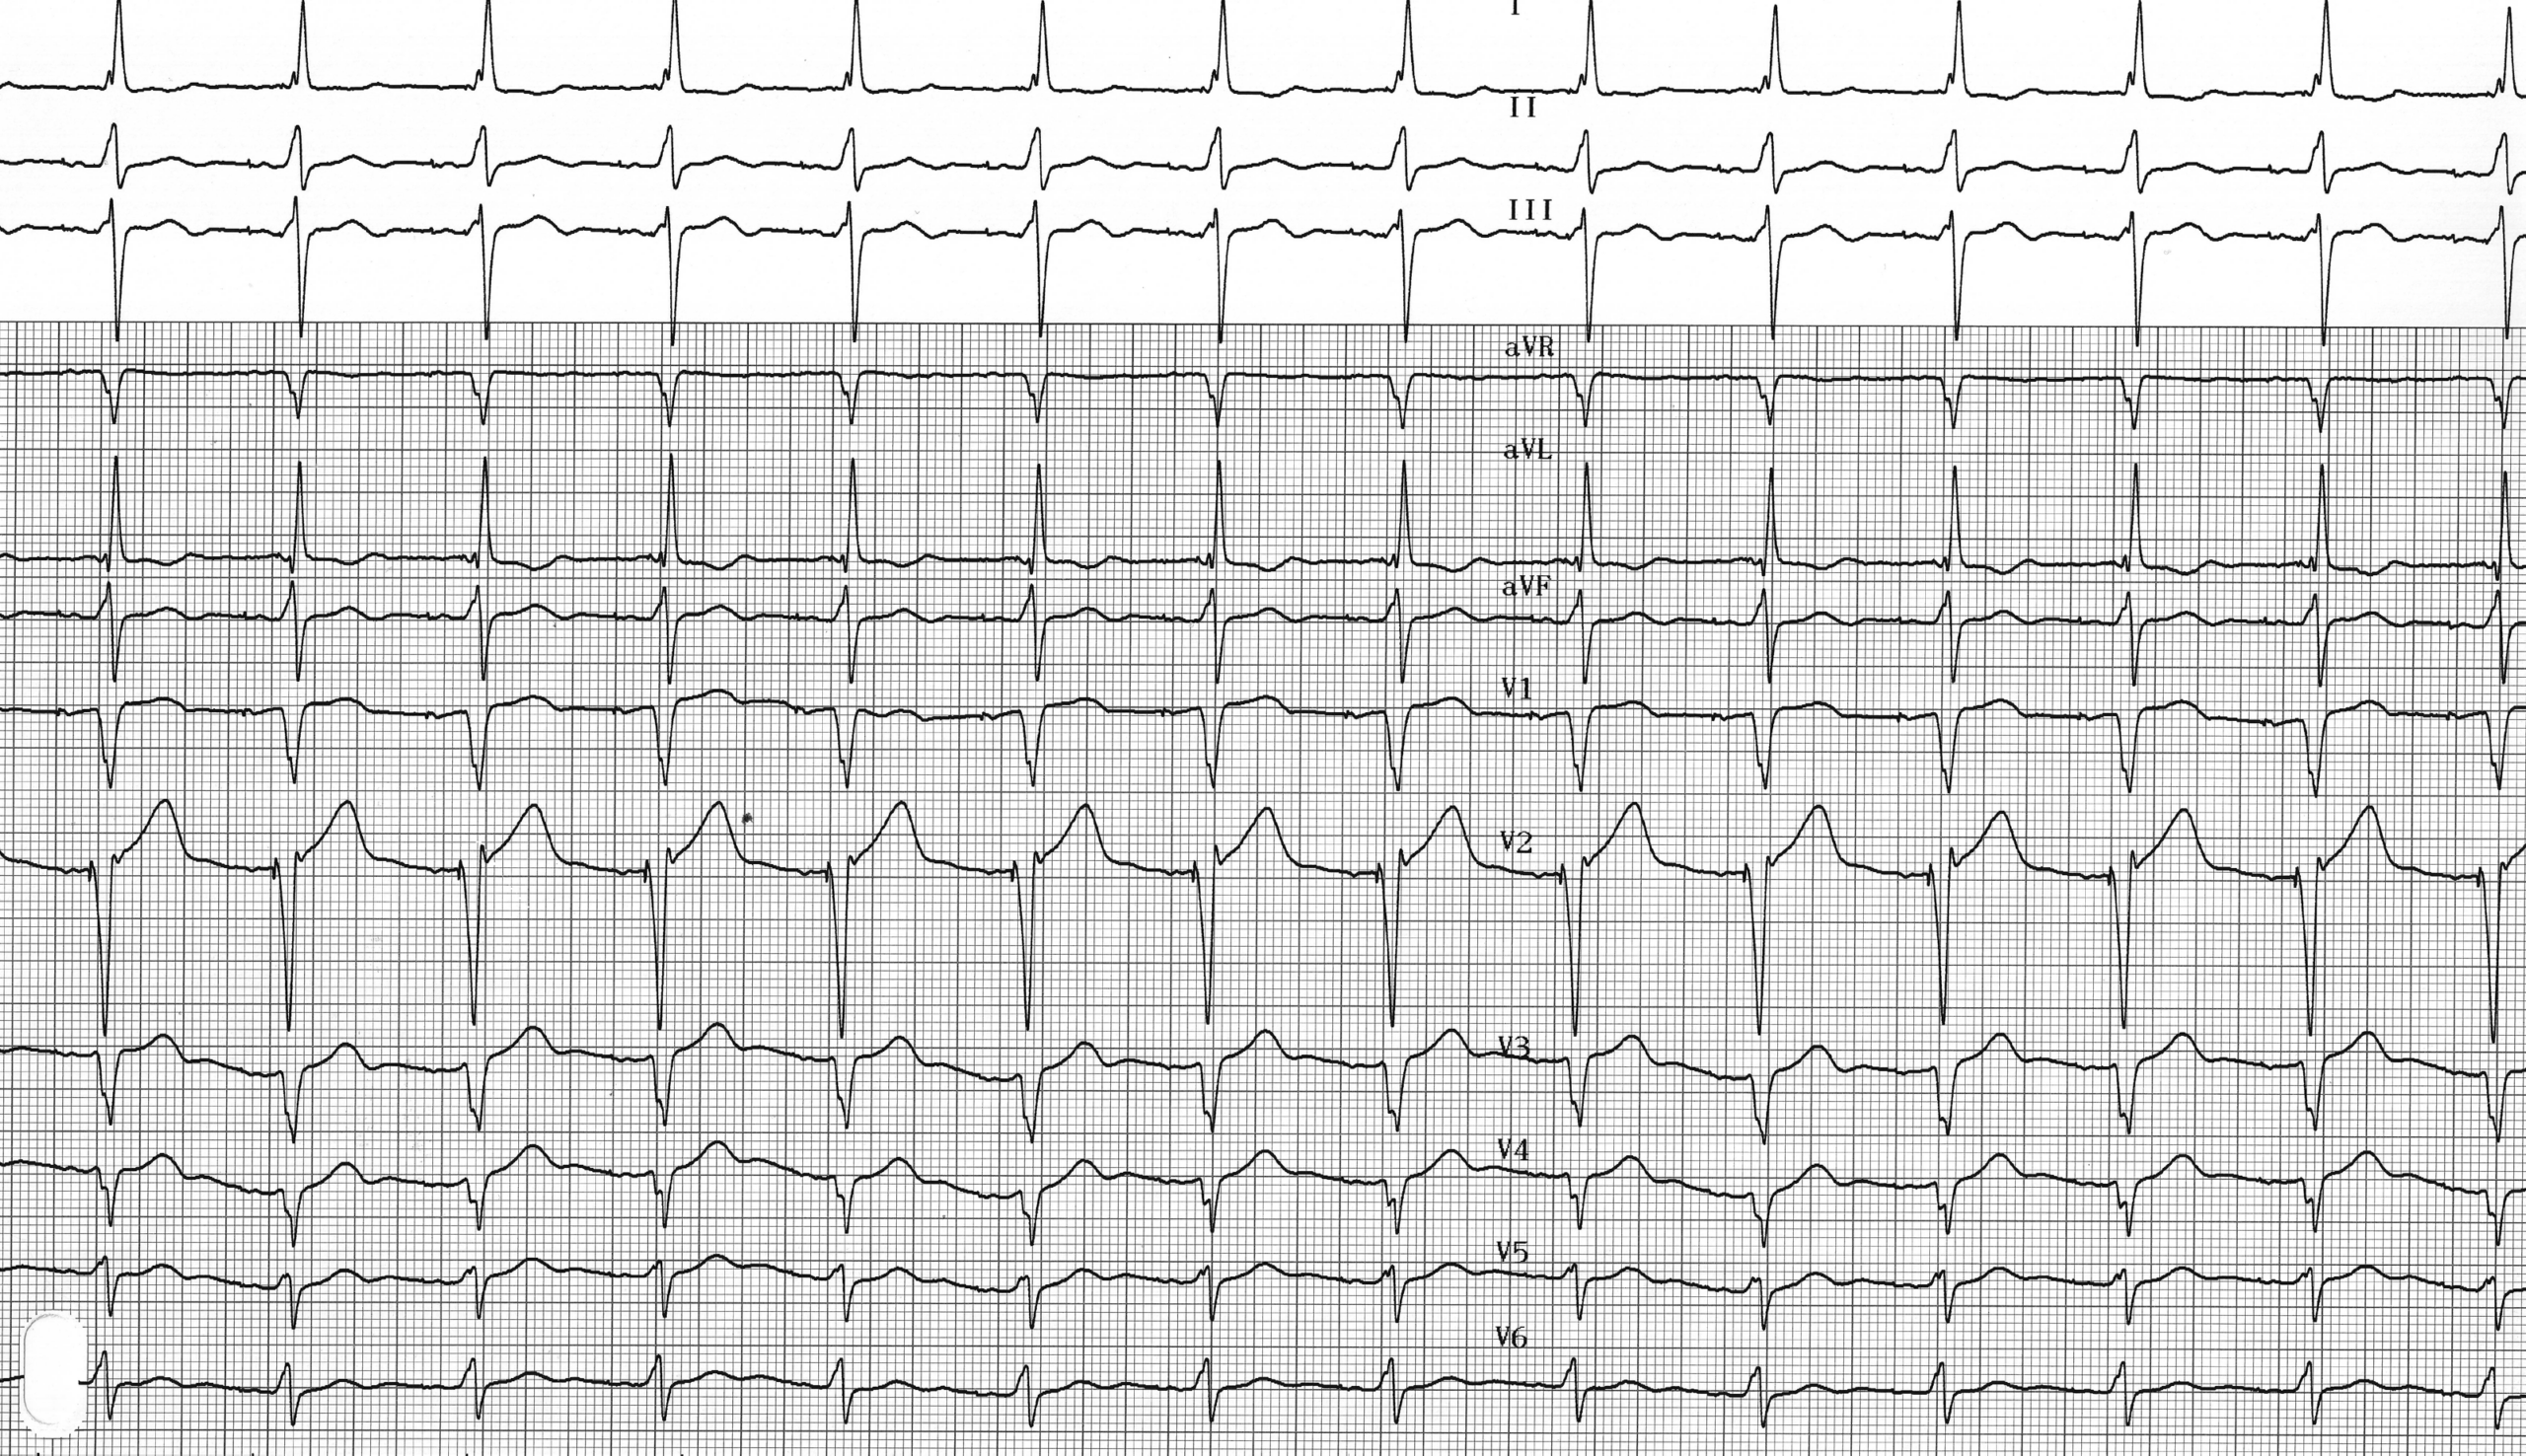

Description tracé

Tracé identique mais stimulation atriale et ventriculaire en mode unipolaire;

Une stimulation unipolaire peut être facilement identifiée sur le tracé électrocardiographique par la grande amplitude des stimuli. Il est à noter que la stimulation est forcément bipolaire pour un défibrillateur implantable.